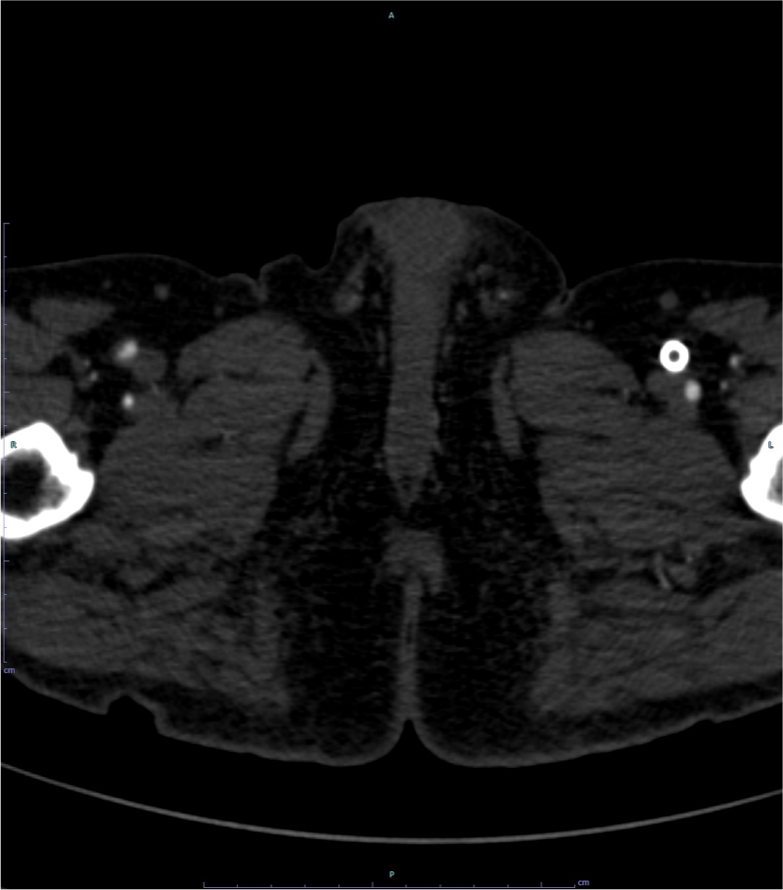

図3.下肢造影CT(左SFAステント近位部レベル)

テント内の造影効果が消失しており、閉塞が認められる